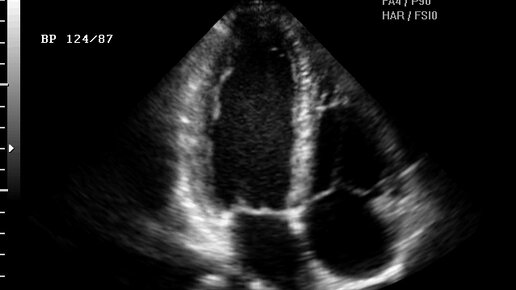

Иногда кажется, что сердце начинает жить своей жизнью: то забьётся учащённо, то будто «пропустит» удар, то внезапно замирает. Эти ощущения пугают, особенно если они появляются неожиданно — например, ночью или в состоянии покоя. Хорошая новость: чаще всего такие перебои не опасны. Но бывают случаи, когда это сигнал о сбое в работе сердца. Разбираемся, что на самом деле происходит, какие причины бывают у таких ощущений и когда стоит идти к врачу. Путаница начинается уже на первом этапе: человек ощущает...